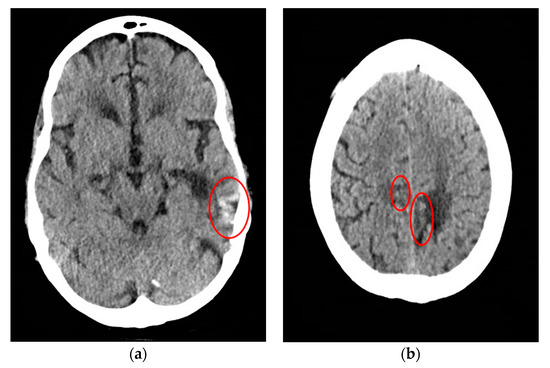

CT scan of the head was reassuring, showing no significant changes from the patient’s previous MRI, performed one month prior to this hospitalization. Unchanged lesions include: small inferolateral left temporal density, associated white matter low density, small medial right and left parietal occipital low densities, and a posterior cerebral white matter hypodensity (Figure 1). Patient’s EEG result read: abnormal EEG due to mild to moderate diffuse slowing, with excess low-moderate voltage polymorphic delta and theta activity (Figure 2).

Figure 1. Computed tomography (CT) head of a 61-year-old male with SCNS-DLBCL presenting with acute encephalitis. (a) CT Head shows a small area of inferolateral left temporal density, which correlates with the blood products that were seen in patient’s previous magnetic resonance imaging (MRI) associated with the temporal lobe lesion. There is associated white matter low density, which is similar to the non-enhancing signal on previous MRI; (b) CT Head shows a small area of medial left parietal occipital low density corresponds to the lesion and old blood seen on the MRI. It also shows a very small area of medial right parietal occipital low density corresponds to signal seen on the MRI.